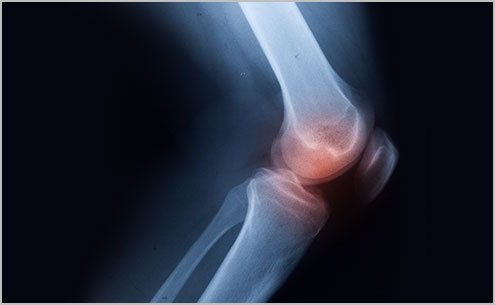

¹«¸ °üÀý(½½°üÀý)¿¡´Â Àü¹æ½ÊÀÚÀδë, ÈĹæ½ÊÀÚÀδë, ³»ÃøºÎÀÎ´ë ¹× ¿ÜÃøºÎÀδëÀÇ 4°¡Áö Àδ밡 ÀÖ¾î ÀüÈÄ¹æ ¹× ³»¿ÜÃøÀÇ ¾ÈÁ¤¼ºÀ» ÁöÄÑÁÖ´Â ¿ªÇÒÀ» ÇÕ´Ï´Ù. °úµµÇÑ ¿îµ¿À̳ª ¿Ü»óÀ¸·Î ½ÊÀÚÀδ밡 Âõ¾îÁö°Å³ª ÆÄ¿µÈ »óŸ¦ ½ÊÀÚÀÎ´ë ¼Õ»óÀ̶ó°í ÇÕ´Ï´Ù.

´ëºÎºÐ ¿îµ¿ Áß ¿Ü»ó¿¡ ÀÇÇØ ¹ß»ýÇϸç, ¿ÜºÎ·ÎºÎÅÍÀÇ Ãæ°Ý¿¡ ÀÇÇØ ¹«¸ °üÀýÀÌ µÚƲ¸®¸ç ¾ÈÂÊ, ¹Ù±ùÂÊ, ¾ÕÂÊÀ¸·Î ½ÉÇÏ°Ô ²ªÀÌ´Â °æ¿ì ¹ß»ýÇÕ´Ï´Ù. Ã౸³ª ³ó±¸, ½ºÅ° µîÀÇ ¿îµ¿ Áß¿¡ ºü¸¥ ¼Óµµ·Î °©Àڱ⠸ØÃ߰ųª ¹æÇâÀ» ¹Ù²Ü ¶§ »ó´ë¹æ ¼±¼ö¿Í Ãæµ¹ ½Ã, Á¡ÇÁ ÈÄ ÂøÁöÇÒ ¶§, ±³Åë»ç°í ½Ã ÁÖ·Î ¹ßº´ÇÕ´Ï´Ù.

ºÎºÐ ÆÄ¿ÀÎ °æ¿ì¿¡´Â Áõ»óÀÌ ½ÉÇÏÁö ¾Ê½À´Ï´Ù. ¹«¸ ³»ºÎ¿¡¼ Àδ밡 ¶ÒÇÏ°í ²÷¾îÁö´Â °ÍÀ» ´À³¥ ¼ö ÀÖ°í ÅëÁõÀ¸·Î º¸ÇàÀÌ ºÒ°¡´ÉÇϱ⵵ ÇÕ´Ï´Ù. ¹«¸ ³» °üÀý¿¡¼ ÃâÇ÷ÀÌ »ý±â¸ç ºÎÁ¾°ú ¹«¸ ÁÖÀ§¿¡ °ËǪ¸¥ ¸ÛÀÌ »ý±â±âµµ ÇÕ´Ï´Ù. ¹«¸ÀÇ ¾ÈÁ¤°¨ÀÌ ¶³¾îÁ® ¼ Àְųª ³»µóÀ» ¶§ ¹«¸ÀÌ ÁöÅÊÇÏÁö ¸øÇÏ°í °©Àڱ⠱¸ºÎ·¯Áö´Â Áõ»óÀÌ »ý±é´Ï´Ù.